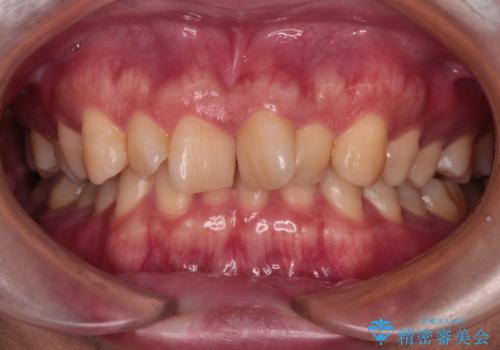

- 前歯のデコボコと深い咬み合わせを気にして来院された患者様です。

骨格的に上顎骨がやや前方にあり、それが原因で下顎前歯が隠れるほどのディープバイトになっている状態でした。